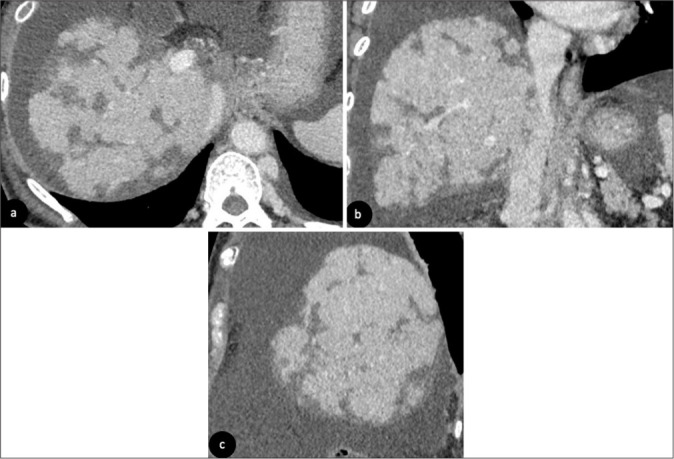

在过去的几十年里,化疗的使用彻底改变了癌症的治疗。肝毒性在不同类型的化疗药物中普遍存在。这篇图片综述的目的是阐明各种化疗相关肝实质改变在不同成像方式下的放射学特征,并通过代表性病例展示这些肝损伤模式的潜在并发症。早期识别这些肝脏疾病可以及时采取临床行动,从而优化管理并避免严重并发症。

The use of chemotherapy has revolutionized the management of cancer in the past decades. Liver toxicity is commonly observed among different types of chemotherapy drugs. The aim of this pictorial review is to illustrate radiological features of various chemotherapy-associated hepatic parenchymal changes in different imaging modalities and to demonstrate potential complications of these liver injury patterns with representative cases. Early recognition of these liver conditions allows prompt clinical action to be taken, thus optimizing management and avoiding severe complications.